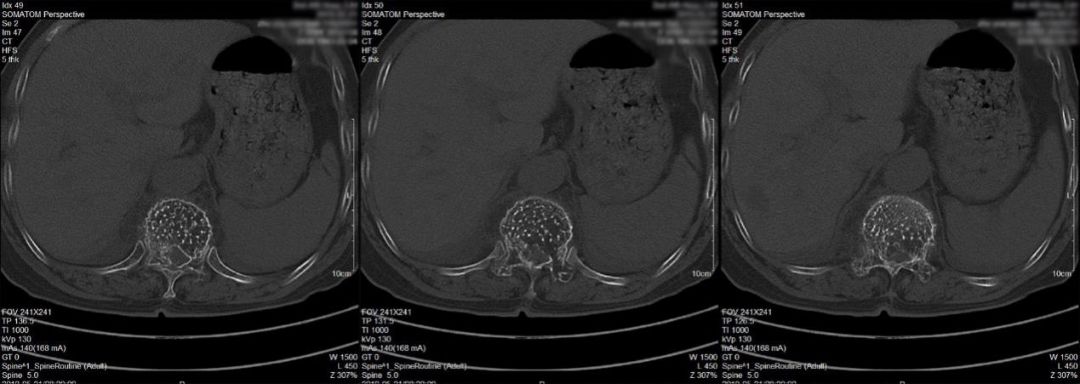

影像学检查:胸椎增强MRI提示胸11椎体及附件骨骨质破坏,呈膨胀性改变,椎体内间栅栏状纵行骨小梁存留(图1);胸椎CT平扫提示病变累及胸11全椎体及附件,表现为蜂窝样骨质改变。胸11椎体及两侧椎弓根、横突骨质密度减低,呈栅栏状改变,椎体向四周膨隆,椎管狭窄,椎旁软组织肿胀。胸12、腰1楔形变(图2)。

图1.术前胸椎增强MRI检查提示胸11及颈7病变,考虑血管瘤可能,转移性肿瘤待排。胸11病变继发病理性骨折,椎管狭窄,脊髓受压。